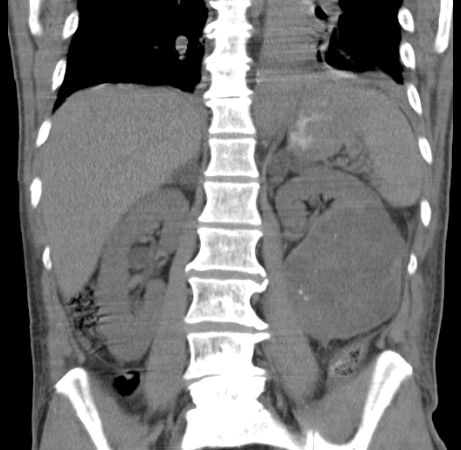

61-jähriger Mann bei dem notfallmäßig eine Tumornephrektomie links wegen Sepsis und nekrotisch zerfallendem, infiziert rupturiertem NZK links cT3b pM0 M0 G2 durchgeführt wurde. Makroskopie: 15 x 9 x 10 cm großes Nephrektomiepräparat. Im Zentrum überwiegend im Hilusbereich entwickelt, ein stark nekrotisch zerfallender, 8 cm großer Tumor.

Mikroskopie: Der Tumor zeigt papilläre, teilweise tubuläre Strukturen.

Die Einzelzellen enthalten vergrößerte hyperchromatische Zellkerne mit prominenten Nukleolen.

Das Zytoplasma ist teilweise klar, teilweise schwach eosinrot angefärbt.

Teilweise erkennt man Tumoranteile mit girlandenförmigen Proliferaten.

Immunhistochemie: z.T positiv mit CD 10. Herdförmig kräftig positive Reaktion mit Zytokeratin 7 und Vimentin. CD 117, Melan A und HMB 45 negativ.

5 Monate später Rezidiv. Th.:Pazopanib